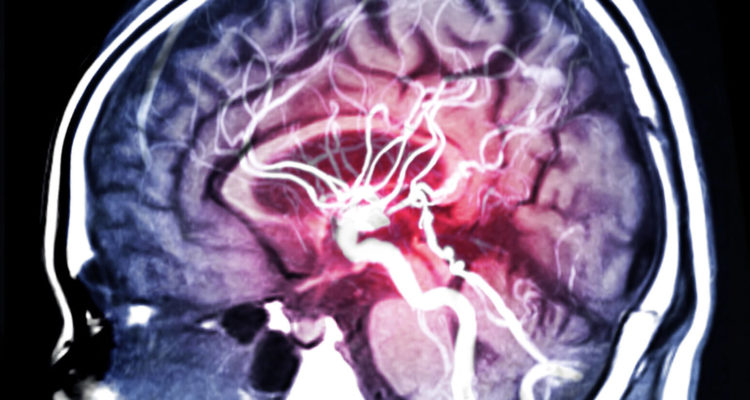

Імовірність смерті жінок до 1 року після першого інсульту була на 39% вище. Згідно з новим дослідженням, опублікованим в журналі жіночого здоров’я, різниця між статями пояснюється літнім віком і більш важкими інсультами у жінок.

Серед жінок і чоловіків, які вперше перенесли інсульт, жінки були приблизно на 7 років старше. Крім того, на 9,3% менше жінок могло ходити самостійно при вступі до лікарні, що свідчить про більш важкому інсульті.

Серед померлих з будь-якої причини у чоловіків було більше смертей від раку (12% проти 6% жінок) і ішемічної хвороби серця (8% проти 6% жінок), в той час як у жінок було більше смертей, пов’язаних з інсультом (50% проти 41% чоловіків. ) або інші серцево-судинні захворювання (16% проти 13% чоловіків), заявляє Домінік Каділак, доктор філософії, Школа клінічних наук в Monash Health, і співавтори.

“Каділхак та його колеги показали, що ризик смерті жінок, пов’язаних з інсультом, на 65% вище. У жінок не тільки більше шансів бути старше при першому інсульті і мати більшу ступінь тяжкості інсульту, але вони також рідше отримують аспірин від вторинна профілактика інсульту”, – говорить Сьюзен г. Корнштейн.